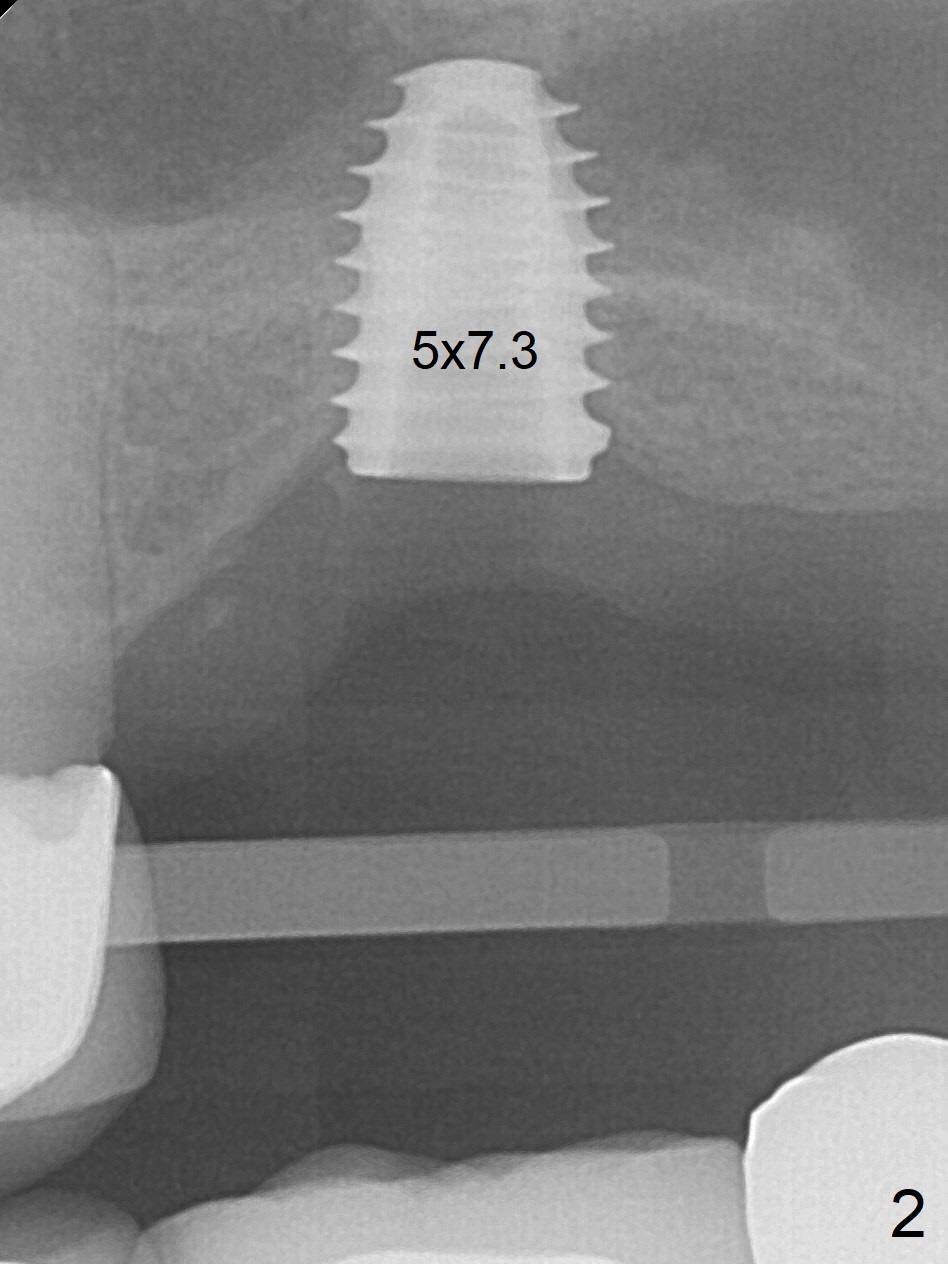

When the non-osteointegrated implant is removed, the sinus membrane is found to have been perforated. There is a history of clear discharge immediately postop ~ 1 year ago. Against the common wisdom, a 5x10 mm dummy implant is inserted with intention to correct the trajectory and 50 Ncm (Fig.1). With placement of Osteogen plug (presumably for repair of the perforation) and limited amount of Vanilla at the osteotomy, a 5x7.3 mm IS implant with SLA surface treatment is placed (Fig.2, ~ 40 Ncm). When the implant is further seated (Fig.3 arrow with bone graft coronally *)), its trajectory is within the normal limit (Fig.4 blue line). If the implant fails again, it must be due to the mild sinus infection. Bone graft, or preferably Osteogen Plug (collagen with osteoconductive ability) should have been done first. Mild tenderness exists with use of Water Pik 7 months post 2nd placement (Fig.5). Uncover shows that the implant is stable. A 6x3 mm healing abutment is placed. Next appointment a temporary crown will be fabricated for progressive loading. The abutment screw needs retightening 8 months post cementation, probably related to poor crown/implant ratio and missing 2nd molar (Fig.6).